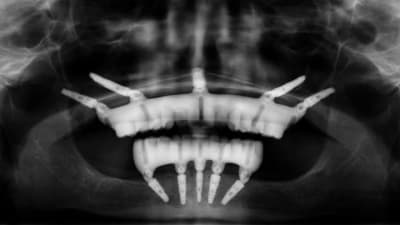

MasterClass Implants Partially Guided Remote Anchorage With a Full-Arch Digital Workflow By Chris Barrett, DDS, Nate Farley, DDS, MS, Kent Howell, DMD, MS A look at using zygomatic and pterygoid implants to restore form and function for patients with severe maxillary atrophy. March 01, 2025 4 min read